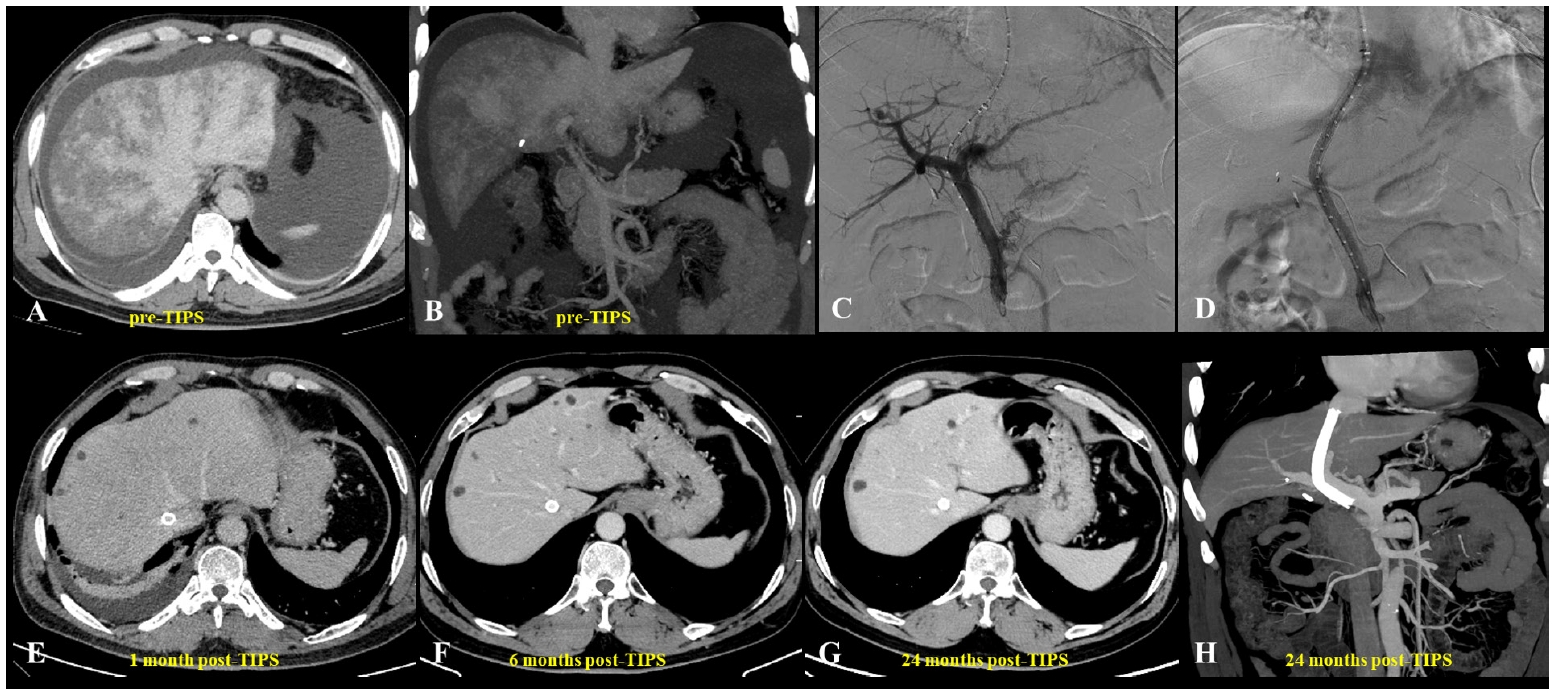

Fig. 1.A 62-year-old man diagnosed with hepatic sinusoidal obstruction syndrome 4 months after ingestion of Gynura segetum. (A) Abdominal computed tomography (CT) during the hepatic venous phase demonstrated patchy parenchymal enhancement with characteristic clover-like enhancement around the hepatic veins. Significant ascites and bilateral pleural effusions were also observed. (B) Coronal CT revealed patchy liver enhancement and narrowing (thinning) of the portal vein, accompanied by abundant ascites. (C, D) Portography before and after transjugular intrahepatic portosystemic shunt (TIPS) creation. A guidewire, introduced via the right hepatic artery, was used to provide real-time guidance during the procedure. (E–H) Post-TIPS abdominal CT showed well-defined opacification of hepatic veins with substantial resolution of both ascites and pleural effusions. Long-term follow-up CT, extending up to 24 months, confirmed homogeneous enhancement of the liver parenchyma and sustained patency of the TIPS shunt.

TIPS has emerged as an important therapeutic option for PA-HSOS patients with refractory PH or ascites, and although it has no specific contraindications for treatment, guidelines recommend considering it for patients with ineffective medical therapy, highlighting the importance of individualized assessment [

15]. Studies have shown that ascites and pleural effusions can markedly improve within a short period after TIPS placement, with previously obstructed hepatic veins often regaining patency in the short term when combined with AT (

Figs. 1,

2) [

10,

52]. Various studies have confirmed the safety and efficacy of TIPS in managing PA-HSOS (